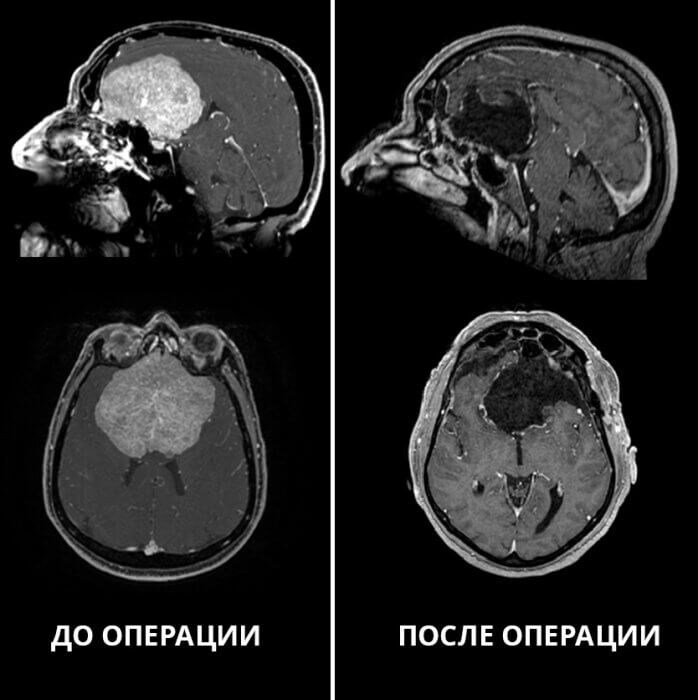

Фото НМИЦ им. ак. Е.Н. Мешалкина.

«Менингиома диаметром 8,5 см располагалась в области передней черепной ямки и очень сильно сдавливала обе лобные доли. Такие большие размеры встречаются крайне редко. По поверхности опухоли и частично в её капсуле проходили крупные магистральные артерии головного мозга: обе внутренние сонные артерии с их ветвями, обе передние мозговые артерии, передняя соединительная артерия, а также – оба зрительных нерва и их перекрёст (хиазма). Повреждение любой из этих артерий или нервов могло привести к самым неблагоприятным последствиям: инсульту, кровотечению, слепоте, тяжёлым нарушениям обмена веществ. Нам предстояло многочасовое, очень кропотливое вмешательство высокого риска, требующее предельной концентрации», — поделился врач-нейрохирург Сергей Чернов.

В результате операции, которая продлилась 8 часов, удалось полностью удалить опухоль, не повредив важных анатомических структур, а также избежать осложнений, не усугубить дисфункцию почки и значительно улучшить качество жизни мужчины. У сибиряка восстановились критичность мышления, когнитивные функции, наладился контроль за мочеиспусканием. У него даже улучшилось зрение, благодаря чему он вновь может читать. Теперь пациенту предстоит малотравматичное транскатетерное вмешательство для восстановления кровоснабжения почки.